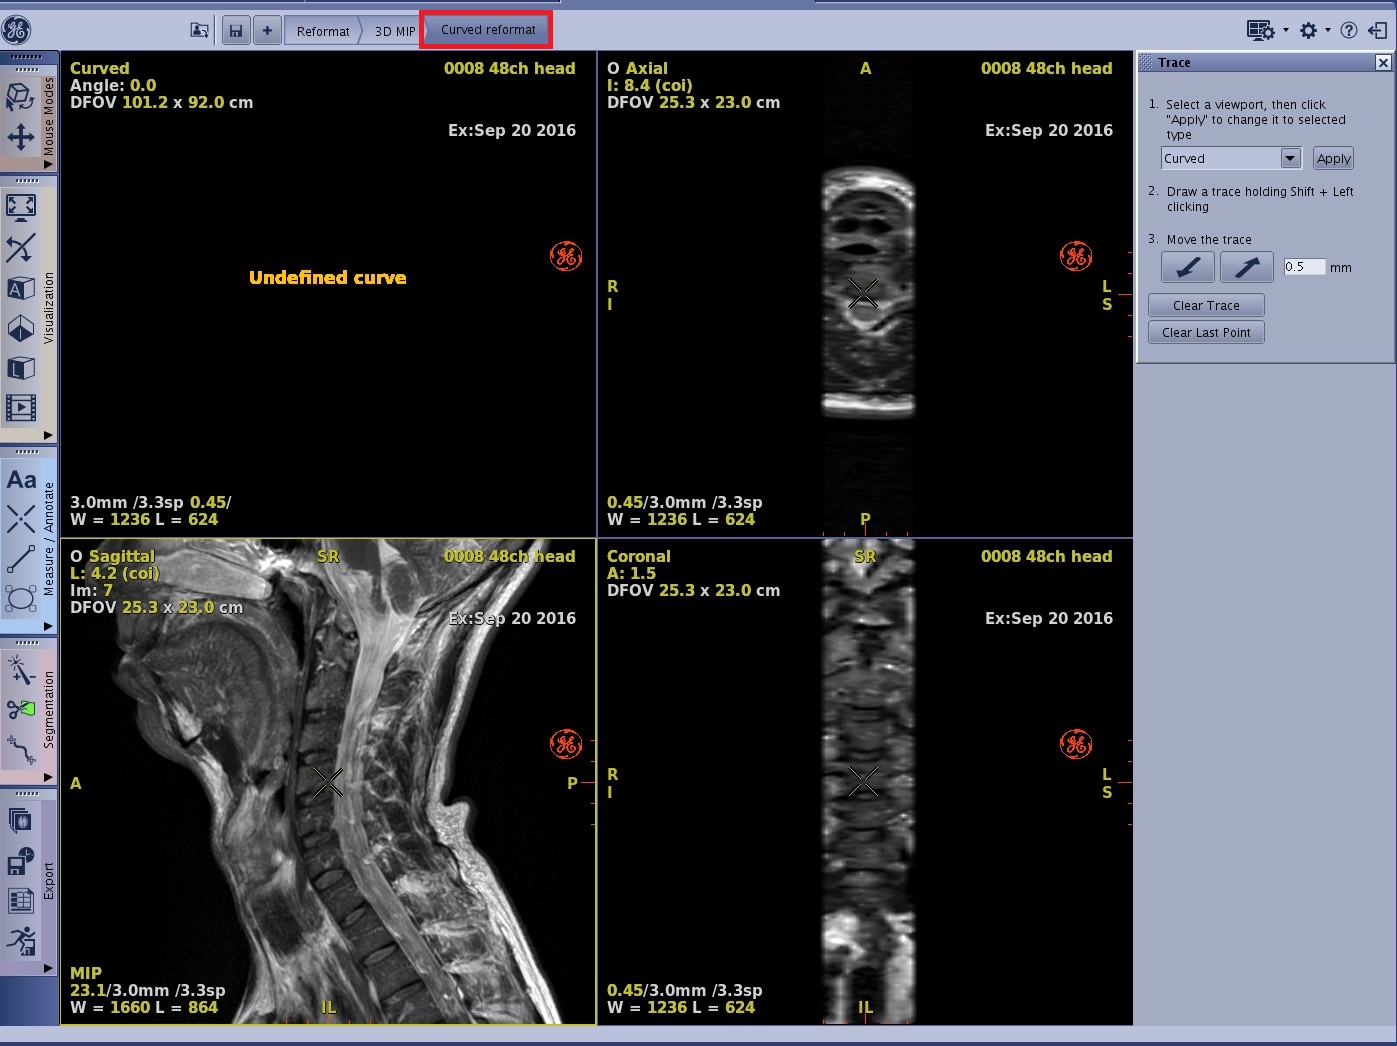

Curved reformat workflow

Use these steps to generate a curved reformatted image.

- From the Review Steps, select Curved Reformat.

Figure 1. The view displays Undefined curve until you start to define the trace

- Place the cursor in the viewport from which you want to define the curve.

- Move the cursor over the starting area, press Shift and click to start your trace. Continue moving the mouse and clicking to deposit points. You can create a trace using more than one image or one plane to encompass a tortuous vessel.

- The curved view shows a reformatted view corresponding to a plane that passes through the trace and is perpendicular to the definition view. This image is updated each time you add a segment to the trace.